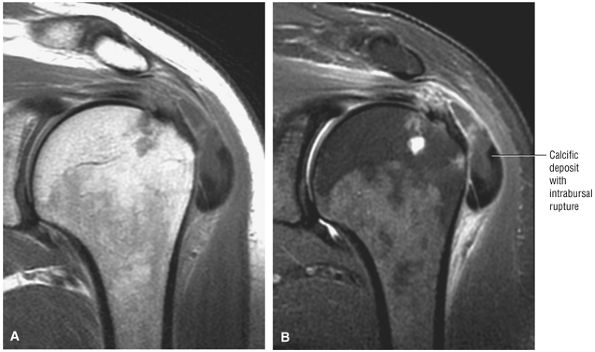

FIGURE 8.102 ● (A) The anterior undersurface of the acromion and the coracoacromial ligament form the coracoacromial arch. The subacromial subdeltoid bursa facilitates the passage of the rotator cuff and proximal humerus under the coracoacromial arch. (B) A superior axial image shows the anterior-to-posterior extent of the coracoacromial (CA) ligament perpendicular to the supraspinatus tendon. The fluid in the subacromial-subdeltoid bursa represents fluid between two serosal surfaces in contact with each other. One serosal surface is contributed by the undersurface of the coracoacromial arch and deltoid, and the other serosal surface is on the bursal side of the cuff.

|

![]() |

FIGURE 8.103 ● Pseudospur. The normal broad attachment of the coracoacromial ligament to the inferior surface of the acromion is shown on (A) T1-weighted coronal oblique and (B) sagittal oblique images. The low-signal-intensity acromial cortex (black arrows) and adjacent coracoacromial ligament and lateral slip of the deltoid attachment (white arrows) give the false impression of a small subacromial spur in the coronal plane. This pseudospur should not be misinterpreted as impingement; otherwise, unnecessary acromioplasties may be performed on patients with a normal coracoacromial ligament attachment and no associated acromial spurs.

-